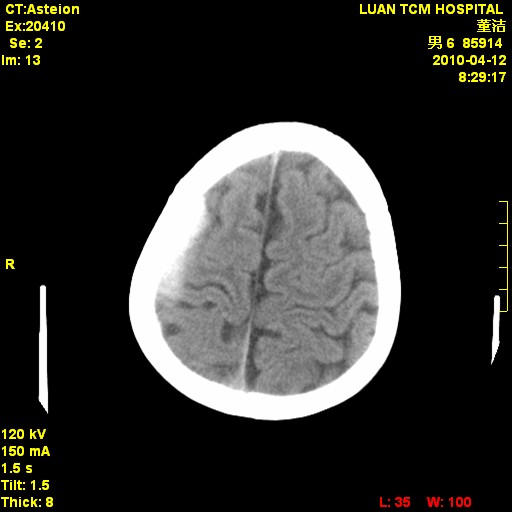

标题: PED3404:有结果,先猜猜这是啥病表现?男,12岁。 [打印本页]

标题: PED3404:有结果,先猜猜这是啥病表现?男,12岁。

考虑右侧额顶部颅内脑外血肿(edh可能)。

右侧额顶部自颅板向内近似半圆高密度影,周围无明显水肿,考虑:脑外血肿?脑膜瘤?淋巴瘤?